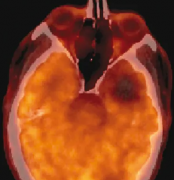

脑海绵状血管瘤症状有哪些?正是由于不同时期出血病灶及其周边脑组织中的含铁血黄素沉积,构成了MRI上海绵状血管瘤特有的影像学表现。除非病灶位于基底核或丘脑,幕上海绵状血管瘤...

脑海绵状血管瘤无症状或者偶然发现,需要手术吗?脑海绵状血管瘤常会因非特异性或无关症状而做影像学检查时被发现(图1)。对于无症状的脑干海绵状血管瘤和单次发作并没有导致严...